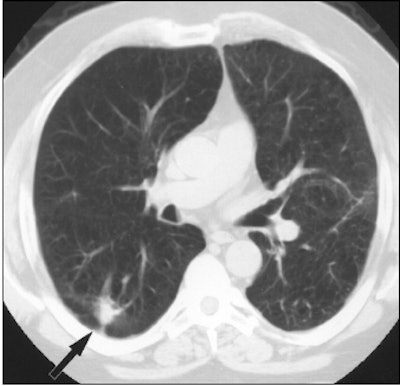

A 62-year-old man with a history of lung cancer and severe emphysema. CT scan (above) shows spiculated nodule (arrow) suggestive of either new primary tumor or recurrent disease. FDG-PET image (below) of thorax shows increased radiotracer uptake of FDG in nodule (arrow). Wedge resection was performed. Nodule was caused by atypical mycobacterial infection. Asad, S, Aquino SL, Piyavisetpat N, Fischman AJ, "False-positive FDG PET Uptake in Nonmalignant Chest Abnormalities," (AJR 2004 182; 983-989).